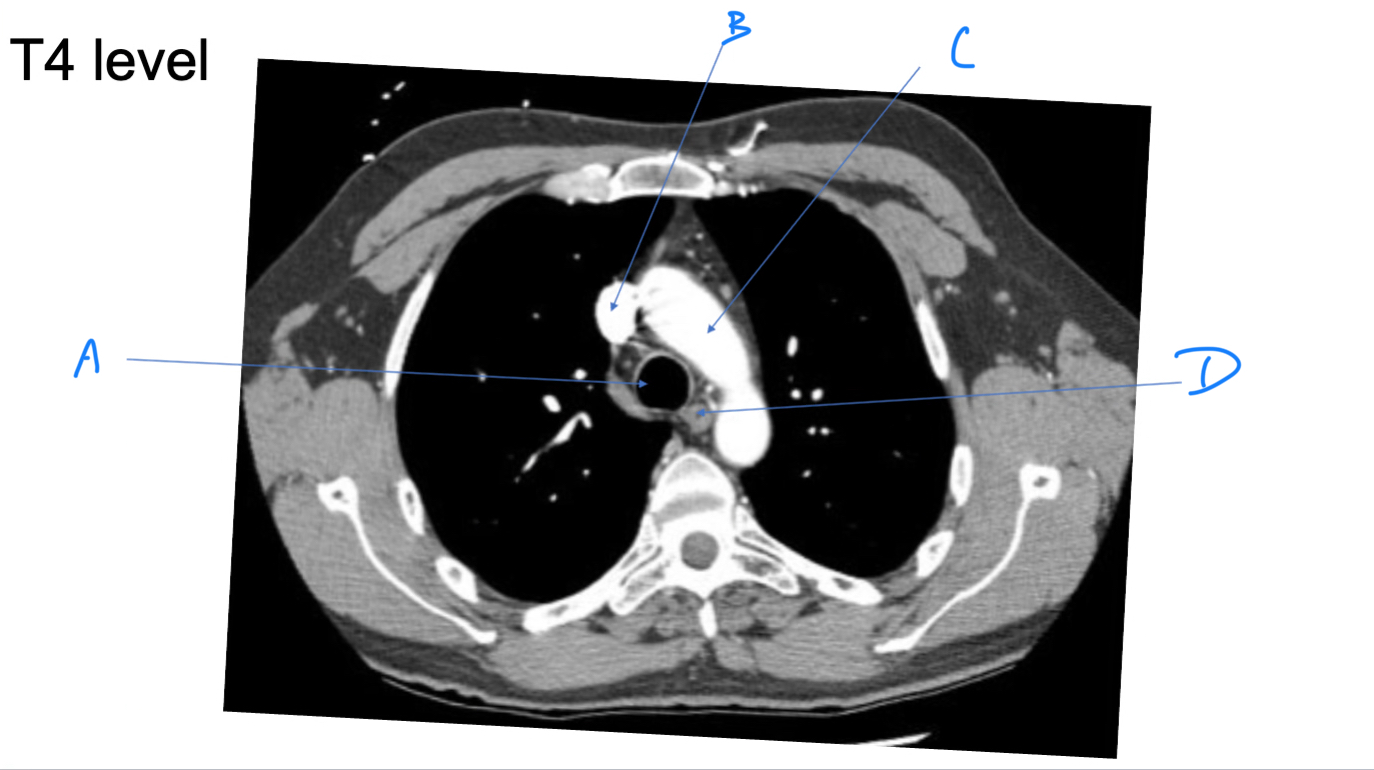

Esophagus

A. Identify

Trachea

B. Identify

R Brachiocephalic v.

C. Identify

Brachiocephalic trunk

D. Identify

L CCA

E. Identify

L Brachiocephalic v.

F. Identify

L Subclavian a.

G. Identify

Trachea

A. Identify

Superior vena cava (SVC)

B. Identify

Arch of aorta

C. Identify

Esophagus

D. Identify